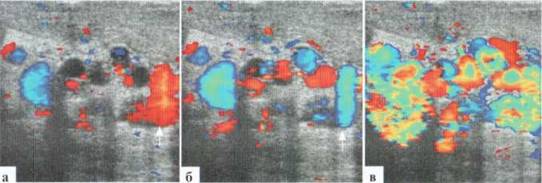

Возможной сложностью визуализации кровотока в венах гроздьевидного сплетения может оказаться его низкая скорость при выраженных степенях варикоцеле: в покое практически не происходит допплеровского окрашивания дилатированных вариксов, и кровоток достоверно может быть зафиксирован только при пробе Вальсальвы (рис. 3.7).

Рис. 3.07. Особенности допплеровской визуализации кровотока в резко дилатированных венах гроздьевидного сплетения: а —в В-режиме определяется выраженное расширение и резкая извитость вен гроздьевидного сплетения; б — ДДС: в покое (клиностаз) в венах гроздьевидного сплетения практически не определяется движение крови, кровоток в яичке сохранен; в — ДДС: проба Вальсальвы. Определяется резкое повышение интенсивности сосудистого рисунка, что связано с повышением скорости кровотока в венах гроздьевидного сплетения. Примечательно, что интенсивность сосудистого рисунка в паренхиме яичка не меняется.

Как уже было отмечено, количественный анализ кровотока в венах гроздьевидного сплетения не имеет принципиального значения: всю необходимую информацию дает качественный анализ кровотока при цветовом допплеровском исследовании: изменение спектра окрашивания и резкое повышение интенсивности окрашивания при пробе Вальсальвы. Кроме того, выполняя пробу Вальсальвы, дети всегда резко напрягают живот, что сопровождается движением всего тела и смещением поискового объема с выбранного сосуда. То есть, попытку выполнения допплерографического исследования обычно приходится предпринимать несколько раз.

При успешной фиксации спектра кровотока определяется изменение его направления, продолжающееся несколько секунд (рис. 3.8). Скорость кровотока в варикозно расширенных венах гроздьевидного сплетения в состоянии покоя в клиностазе может быть минимальной и практически не фиксироваться (см. рис. 3.7), а при пробе Вальсальвы — достигать 10—20 см/сек.